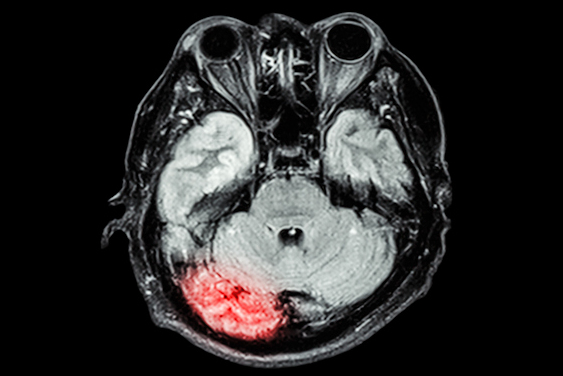

Hyperfine recently updated the AI software for its portable Swoop MRI system. Image courtesy of Hyperfine.